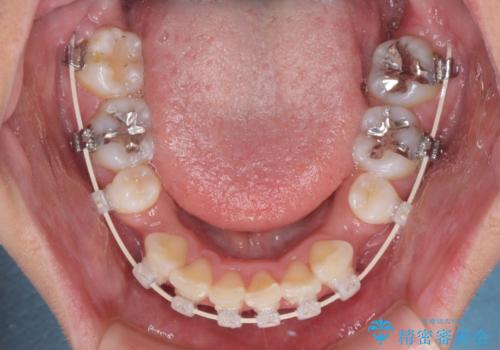

デコボコで飛び出した前歯 ワイヤー装置による抜歯矯正

- 上下前歯のデコボコと、飛び出した前歯を気にして来院された患者様です。

口元を積極的に引っ込めるために、上下左右の小臼歯計4本を抜歯することとしました。

咬み合わせが深く、咬合力強いため、補助装置を使用しながら積極的に口元を下げることとしました。

矯正治療前の咬み合わせで、前歯がすり減ってしまい、歯列が整ったときに先端がガタガタになってしまったため、矯正治療後に形態修正を行いました。